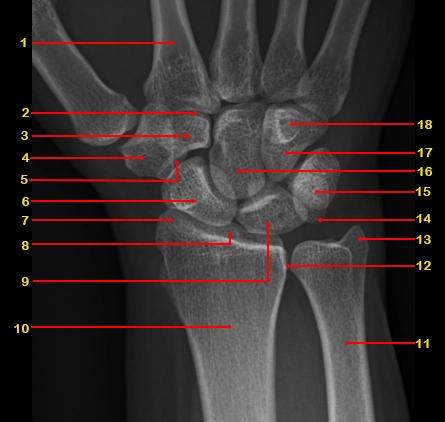

Trả phí

X Quang xương cổ tay

16/03/2026